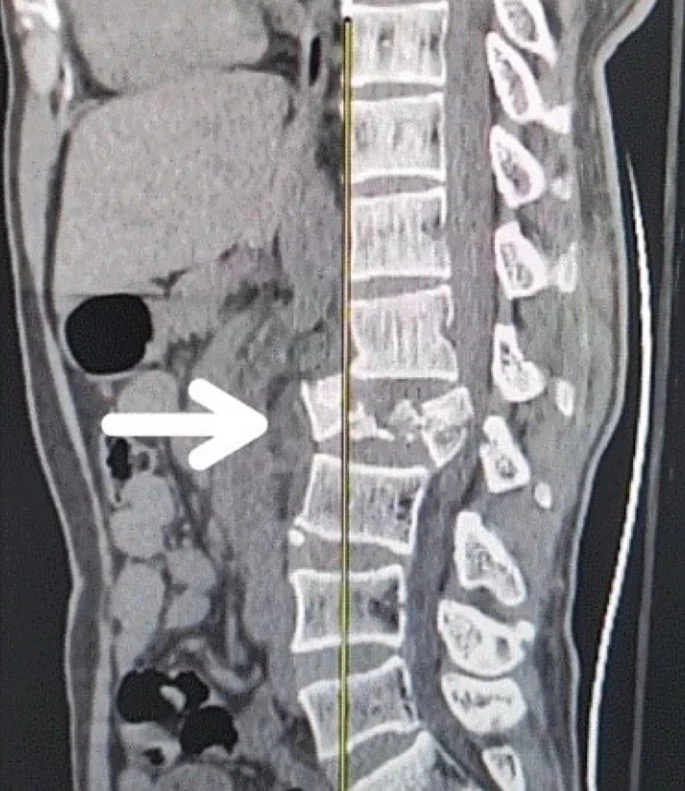

創(chuàng)傷性脊髓損傷是由于脊柱受到突然的強(qiáng)力撞擊,導(dǎo)致椎骨骨折、脫臼、擠壓或壓縮(圖1)。主要原因包括機(jī)動(dòng)車(chē)事故,其中汽車(chē)和摩托車(chē)碰撞占每年新增脊髓損傷病例的近一半。跌倒,尤其是65歲及以上人群的跌倒,是造成脊髓損傷的重要原因,約占60%。體育活動(dòng),例如沖擊性運(yùn)動(dòng)和淺水潛水,約占此類(lèi)損傷的10%。

圖1:X射線(xiàn)圖像顯示脊髓損傷,椎骨骨折和移位,如白色箭頭所示